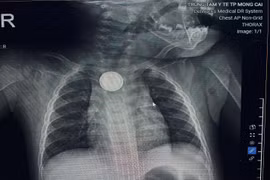

Một bé trai gần 3 tuổi nuốt phải pin cúc áo gây loét thực quản, các bác sĩ cảnh báo tổn thương nguy hiểm khi nuốt phải pin.

Bé 11 tháng tuổi ở Quảng Ninh nuốt pin cúc áo, gây bỏng loét thực quản, nguy kịch phải nhập viện cấp cứu.